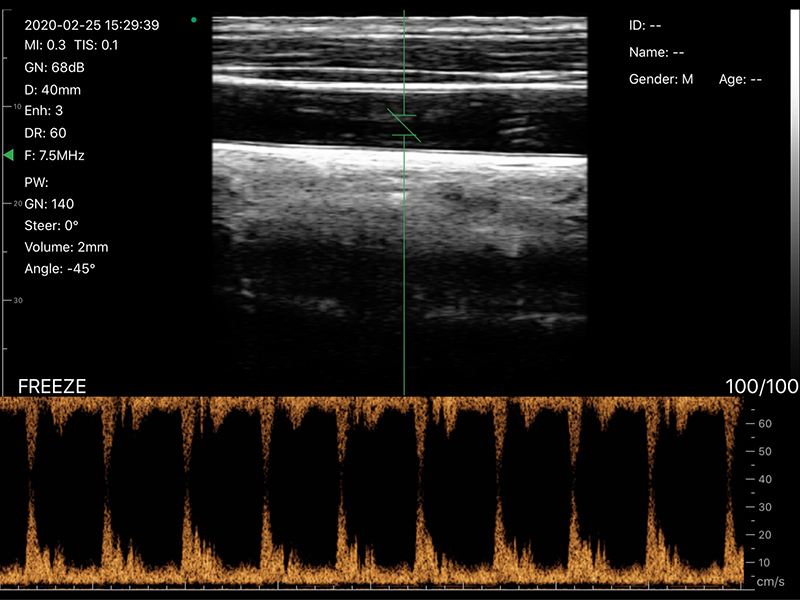

• 显示模式:B、B/M、Color、PW、PDI

• 探头频率:7.5/10MHz

• 扫描深度:20/30/40/55MM,可调